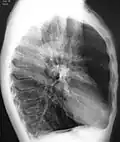

Outros exames

A realização de uma radiografia ao tórax e de um hemograma permitem excluir outras condições no momento do diagnóstico.[69] Os sinais característicos da DPOC observáveis em radiografia são pulmões sobre-expandidos, diafragma achatado e espaço retroesternal aumentado. Ao mesmo tempo, a radiografia permite excluir outras doenças pulmonares, como pneumonia, edema pulmonar ou pneumotórax.[70] Uma tomografia axial computorizada ao tórax permite mostrar a distribuição do enfisema pelos pulmões e pode ajudar a excluir outras doenças pulmonares.[18] No entanto, a não ser nos casos em que se planeie a realização de uma cirurgia, esta distribuição raramente influencia o tratamento.[18] Pode ainda ser realizada uma gasometria arterial para determinar a necessidade de oxigénio suplementar. Este exame é recomendado em pessoas com VEF1 inferior a 35% do previsto, com saturação periférica de oxigénio inferior a 92% e pessoas com sintomas de insuficiência cardíaca congestiva.[17] Em regiões do mundo onde é comum a deficiência de alfa-1 antitripsina, as pessoas com DPOC devem considerar a realização deste exame, sobretudo aquelas com idade inferior a 45 anos e em que o enfisema afeta a parte inferior dos pulmões.[17]